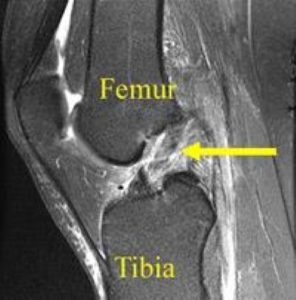

In de meeste gevallen is een MRI-scan aangewezen om de scheur te bevestigen en om bijkomende letsels van kraakbeen, meniscus en gewrichtsbanden op te sporen.

MRI-beeld van een voorste kruisbandruptuur